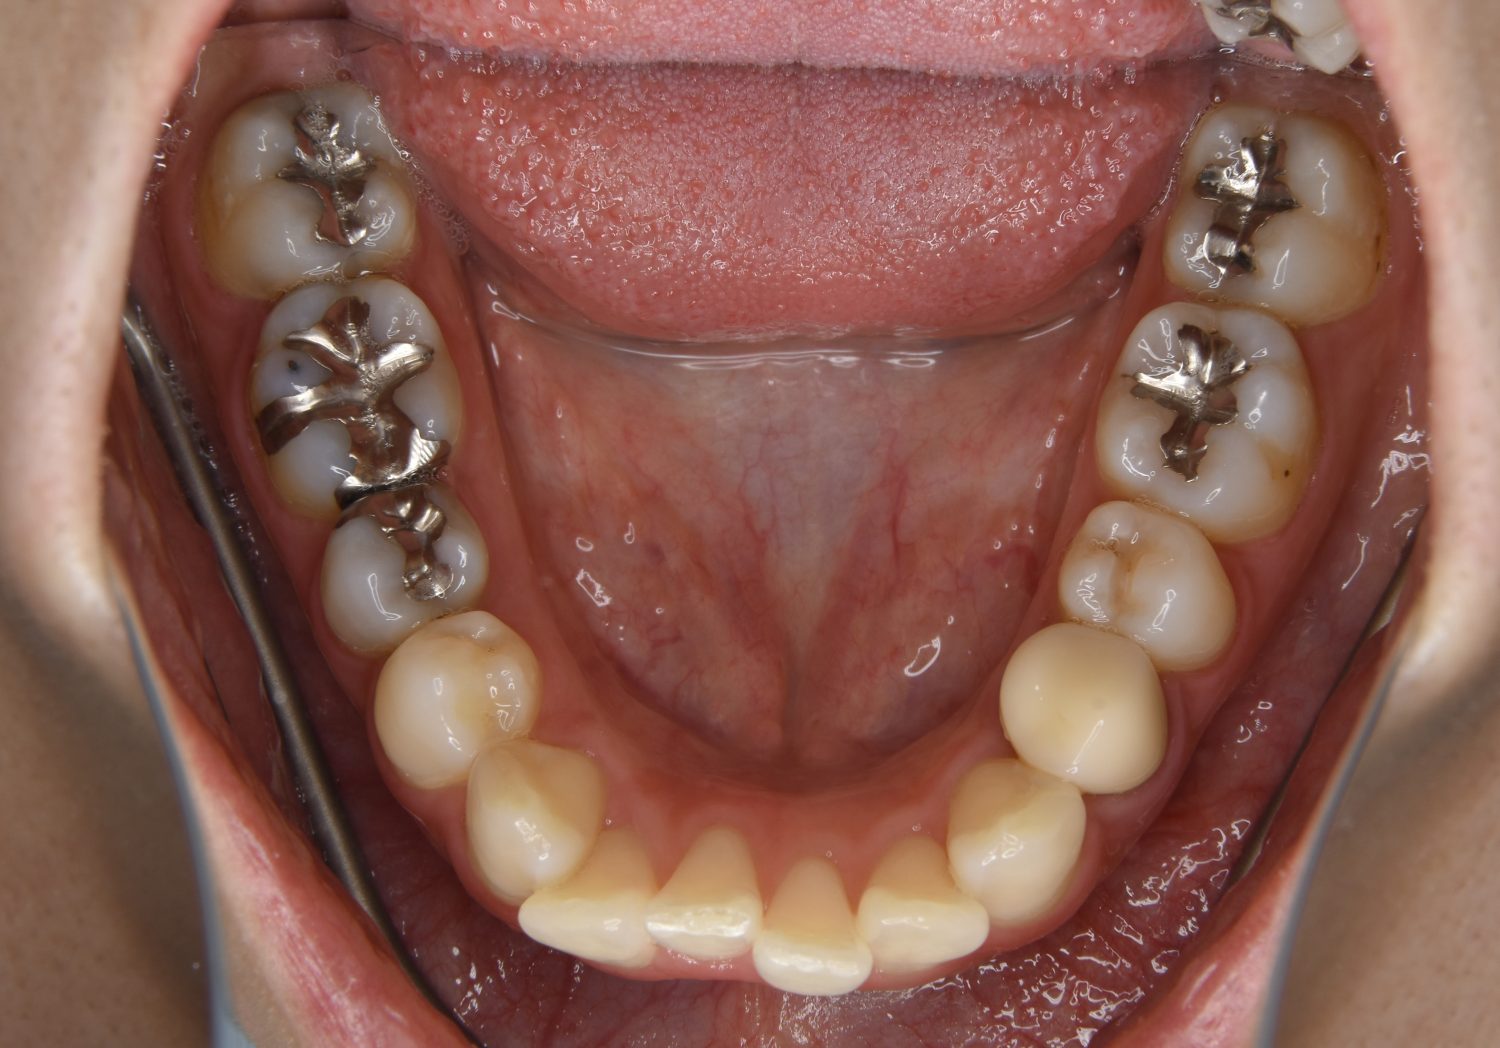

叢生の症例紹介②

Before

After

主訴

歯の凸凹を治したい。

治療内容

アライナー(インビザライン)にて非抜歯で治療を行いました。

治療費

1,150,000 円(税込)

治療期間

26ヶ月

通院回数

14回

想定されたリスク

※歯根吸収、歯肉退縮、歯髄壊死、顎関節症状

※アライナー(インビザライン)は日本の薬機法未承認の矯正装置であり、医薬品副作用被害救済制度の対象外となる場合があります。

丸山和宏先生

ピーススマイル矯正歯科

上下前歯部に叢生(凸凹)が認められる状態でした。歯列の遠心移動を行うことで機能面および審美面が改善されました。